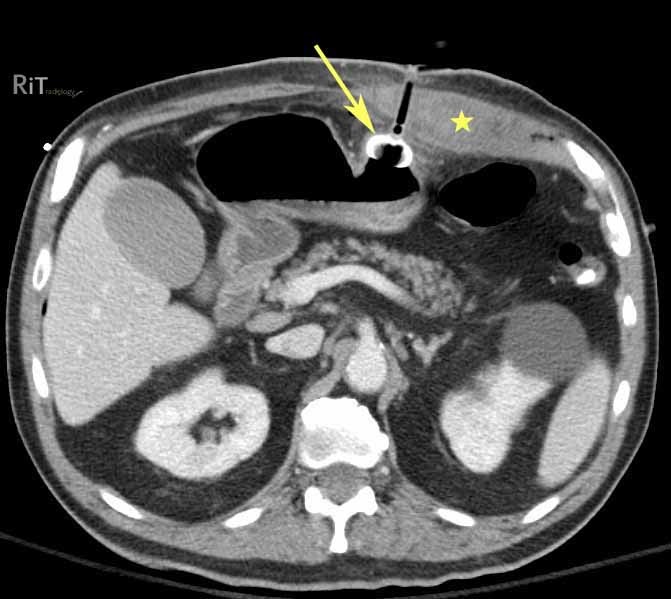

From radiologyinthai.blogspot.com

RiT radiology Rectus Sheath Hematoma Following PEG Placement Peg Tube With Bumper   the parts of a peg tube • external bumper: Peg tubes are about the size of a pen or pencil. You’ll see 6 to 12 inches of the tube coming.   immediately after placement of the peg, the external bumper should be subjected to very low traction, without.   common presenting signs and symptoms include leakage around the peg. Peg Tube With Bumper.